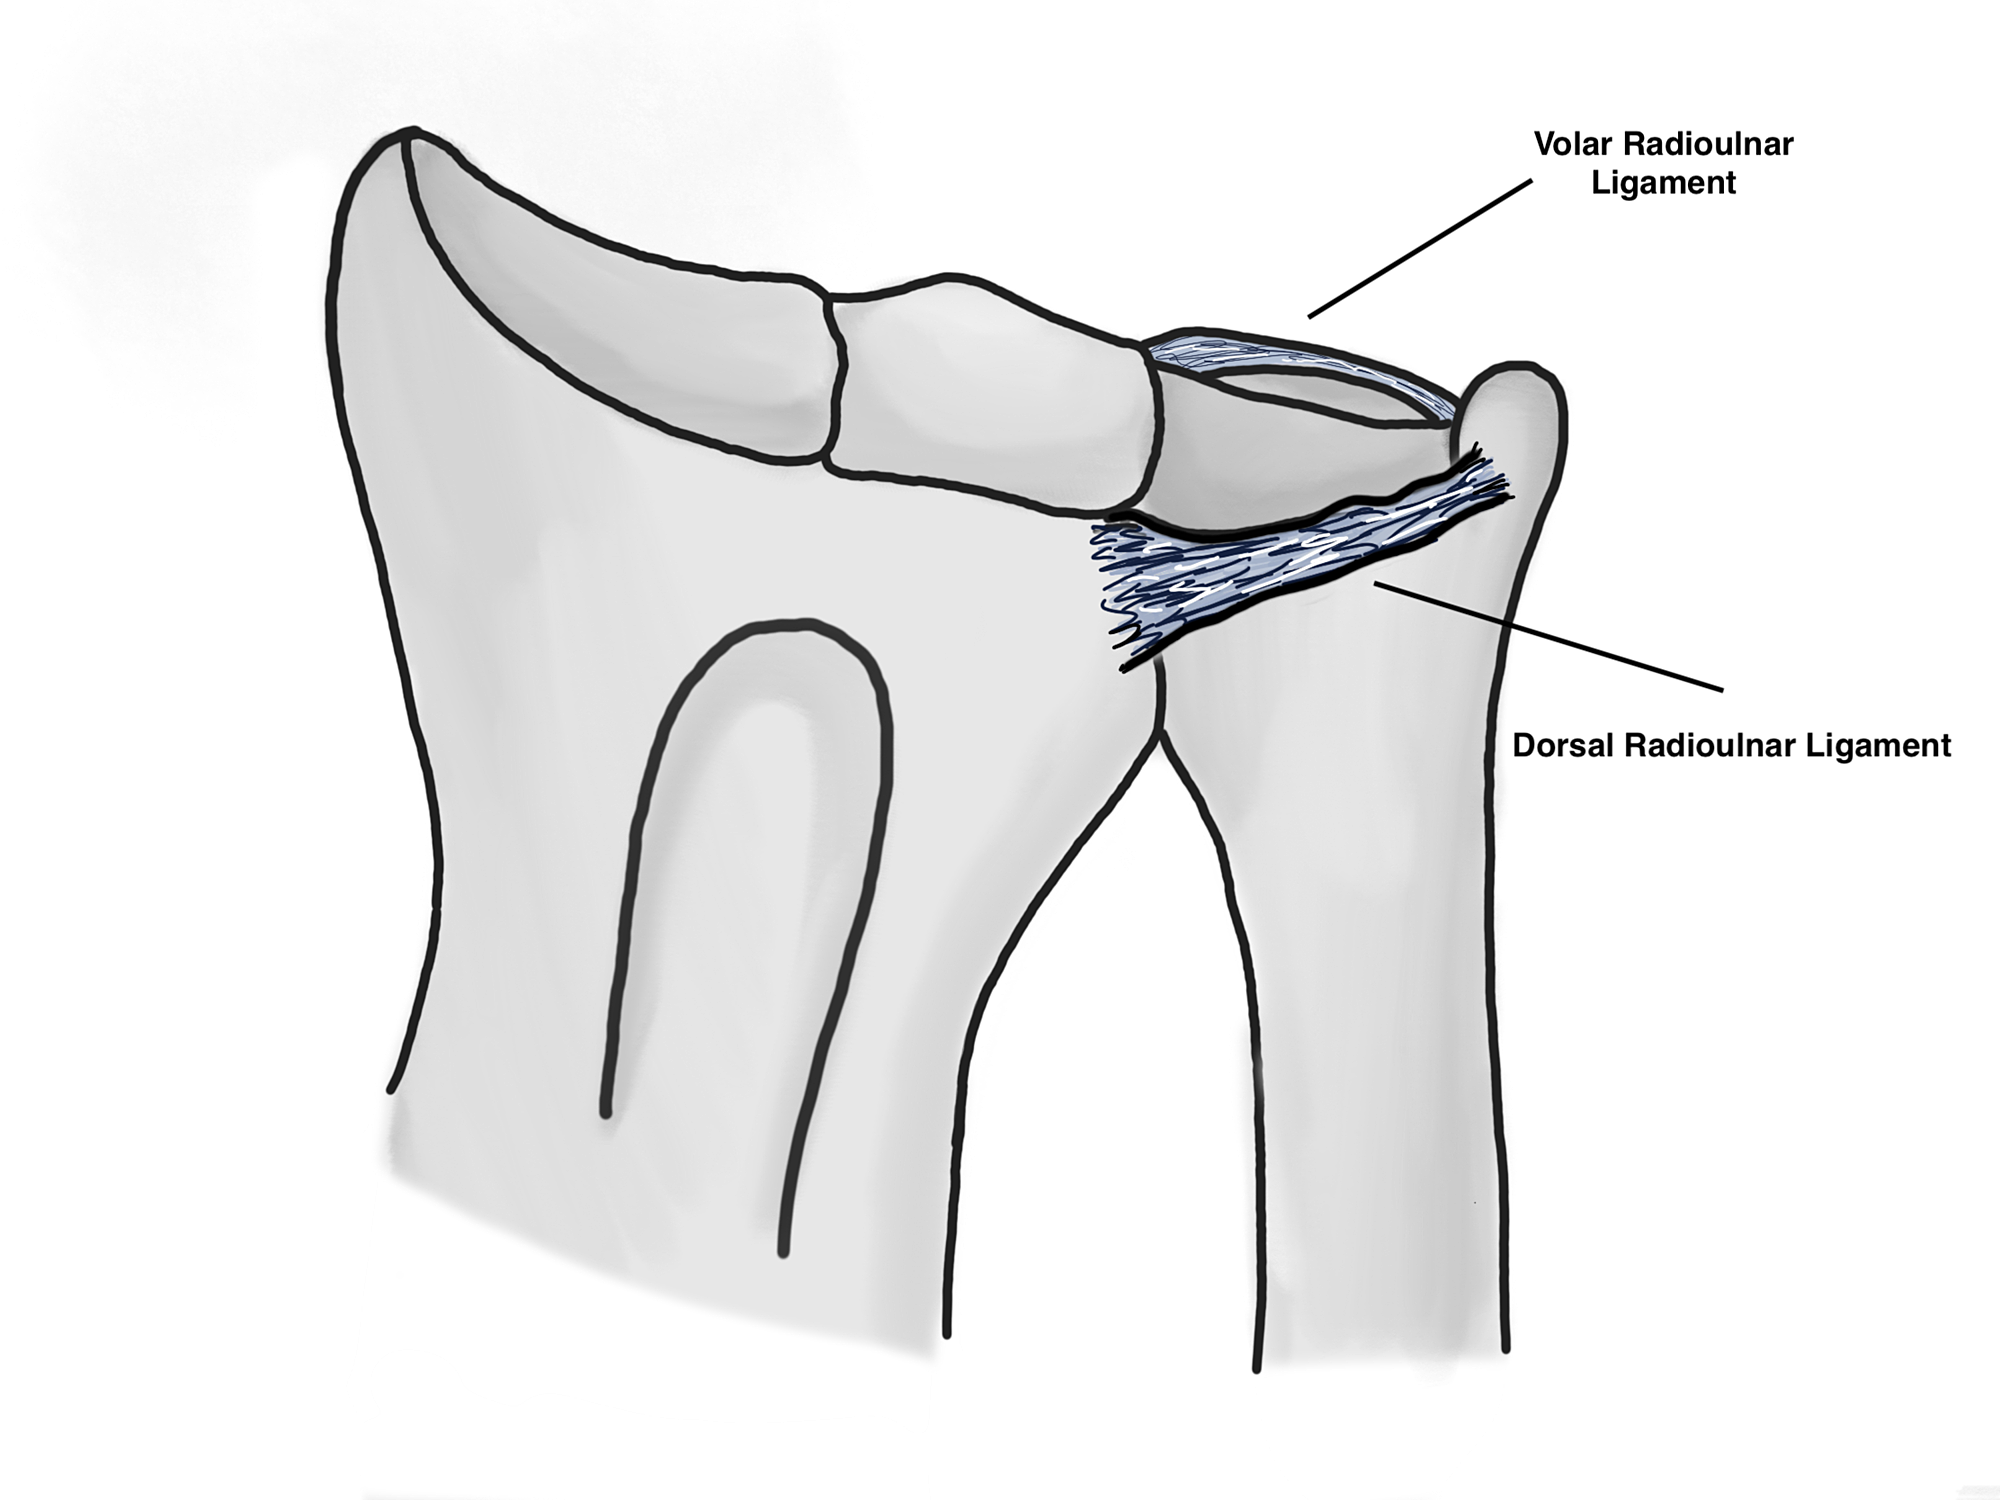

HEP consists of basic education and advice including fracture protection, cast care, and edema control as well as instructions to engage in progressive exercise at home. HEP and SPS are the two most frequently prescribed forms of rehabilitation. What is the effect of rehabilitation protocols (home exercise program versus supervised physiotherapy session ) on functional outcome after DRF, and when should they be initiated? This issue will become increasingly important because of the predicted increase in the number of affected patients and demand for cost-effective healthcare. Despite rehabilitation being critical to the final prognosis of DRF, sufficient evidence of its application and efficacy is lacking. Rehabilitation prevents fracture-related complications and optimizes functional recovery to maintain activities of daily living. However, achieving successful outcomes requires both sound definitive treatment and timely appropriate rehabilitation. Although many studies have focused on immobilization methods or surgical approaches, little attention has been given to rehabilitation protocols during or after those definitive treatments. However, surgical treatment has been increasingly adopted as a reliable modality since the volar locking plate (VLP) was introduced as a robust implant. Nonoperative treatment with a cast remains the most popular treatment for stable fracture. Reduction was satisfactory and fixation strength seemed stable.ĭRF is a very common injury. (C) AP and (D) lateral wrist radiograph after successful operation with a volar locking plate. When the opposite occurs (that is, the radius breaks and shortens), the distal radio-ulnar joint dislocates, resulting in the Galeazzi or "reverse Monteggia" fracture.(A) Anteroposterior (AP) and (B) lateral wrist radiograph of Case 2, an 86-year-old woman with a displaced distal radius fracture whose initial reduction was not maintained within a sugar-tong splint applied in the emergency department. When the ulna is fractured and shortened, the proximal radio-ulnar joint dislocates (the Monteggia fracture). The proximal and distal joints must be carefully scrutinized in every fracture of the forearm. In fractures of the forearm, any shortening of one bone of the forearm necessitates either a fracture of the other with equivalent shortening, or a dislocation at the proximal or distal radio-ulnar joint (Fig 1). Mistakes in their management account for a high incidence of poor results. They are inherently unstable due to a variety of factors which are poorly understood by many surgeons. FRACTURE-dislocations of the forearm are not common injuries.